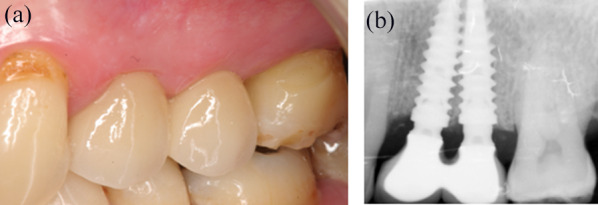

Case presentation: A 57-year-old patient attended with 2 hopeless maxillary premolars. The mesio-distal space available for implant rehabilitation was too narrow to receive standard diameter implants and keep an inter-implant distance (IID) of 3 mm as recommended by accepted guidelines. A protocol of immediate implant placement and provisionalization involving 2 implants of Ø 3.5 mm was implemented; placement in the extraction sockets resulted in an IID of 1 mm. After 3 months of healing the final prosthesis was delivered; the patient has been followed for 10 years now. Surprisingly, the findings showed that the interimplant crest was maintained 1.40 mm coronal to the shoulder of the neck of the implants. Bone completely filled the space between the prosthetic concave abutments and the interproximal papilla was closing the embrasure. The literature reports only 2 experimental studies involving a 1 mm IID; both showed that this did not lead to the resorption of the interproximal bone.